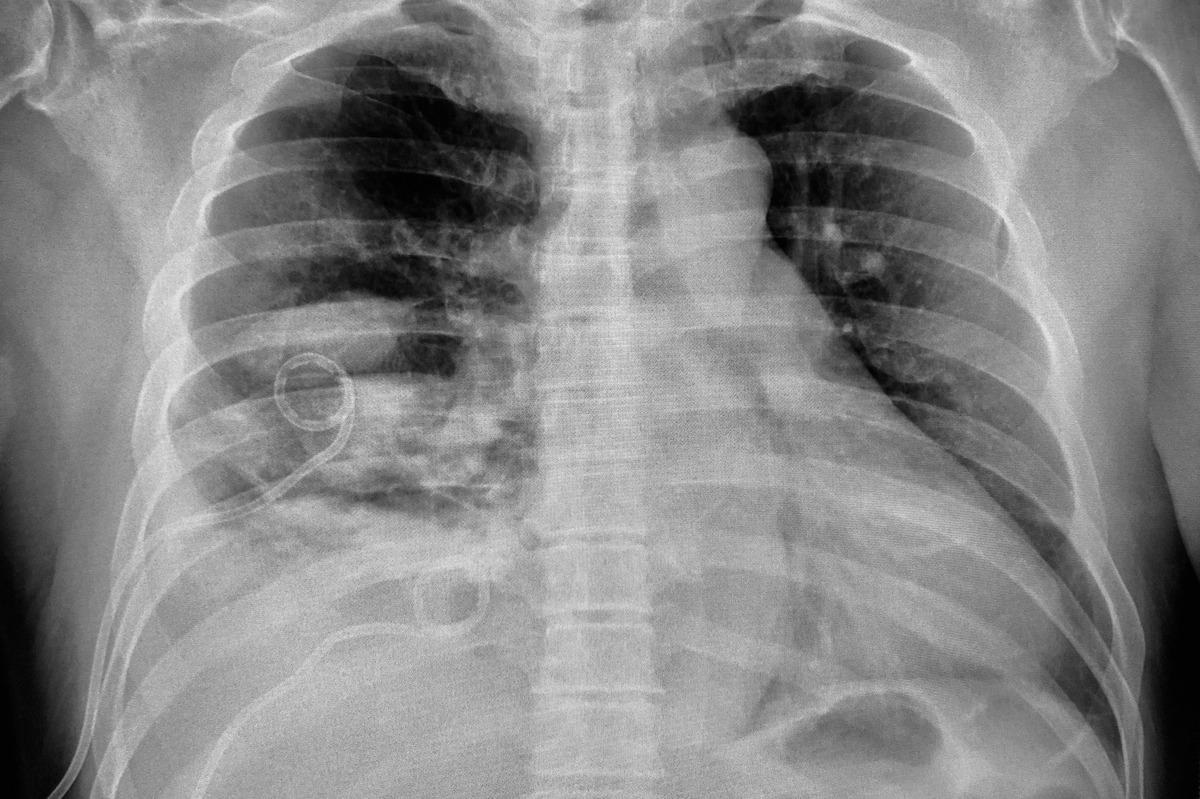

The progression of empyema can be characterized by a series of events. The exudate stage is characterized by an increase in fluid production in the pleural cavity during an inflammatory process such as pneumonia. Microorganisms, most often bacteria, start colonizing the fluid and cause empyema as the disease progresses. This fluid contains higher levels of neutrophils, proteins, lactate dehydrogenase, and dead cells. The fibrinopurulent stage is characterized by a thick opaque fluid. Following the resolution of the infection, as a result of the inflammation, a fibrotic process occurs that can lead to the limitation of the lung parenchyma.

Early intervention and suitable treatment are crucial for minimizing complications and mortality.